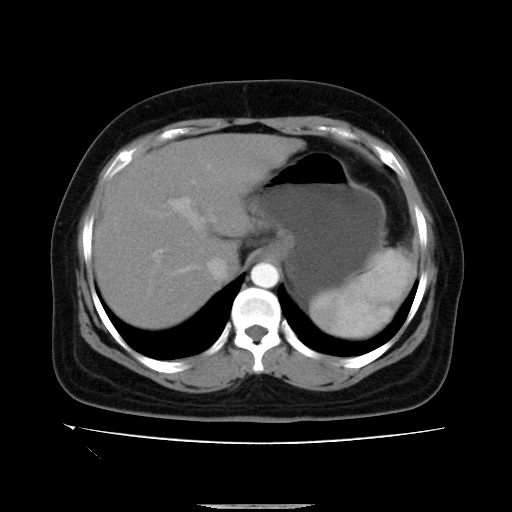

标题: CT14225:女性46岁。当地B超示肝内占位,来我院作CT检查。请 [打印本页]

标题: CT14225:女性46岁。当地B超示肝内占位,来我院作CT检查。请

肝内结节强化特点符合原发性肝癌表现,脾脏改变考虑为增大及先天发育所致。

动脉期病原灶明显强化高于肝密度且中央有无强化区,静脉期强化程度下降明显,延迟低于肝密度,考虑肝腺瘤可能性大,

肝内结节强化特点:快进快出符合原发性肝癌表现

非常典型,肝ca,脾脏先天性发育异常,脾大

此患者虽然符合快进的特点,却不符合快出的特点,因为门脉期几乎是等密度,不符合肝癌的增强表现,所以我考虑肝局灶性结节增生可能性大

肝内结节强化特点符合原发性肝癌表现。脾大。

快进快出,符合肝癌表现。脾脏改变考虑为增大及先天发育所致。